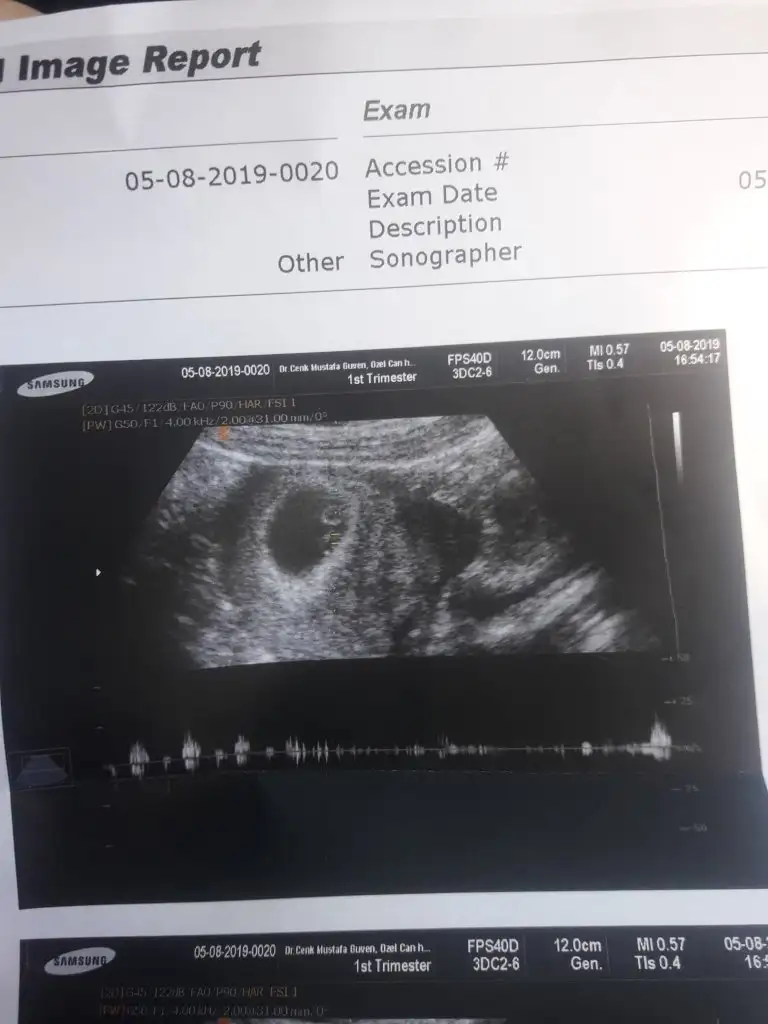

Kağıdının diğer kısmında yazıyor olabilir sağ altta yazıyor geneldeEki Görüntüle 2295859

Kızlarr biz geldikkher sey yolunda çok şükür 8 haftayla uyumlu dedi doktor. Ama doktor çok sevimsizdi ya agzından gramla laf aldık. Bu kağıtta bebeğin boyu nerede yazıyor ben bulamadım da. Geriden gelme olayi düzelmis sanirim doktor 8 hafta dedigine göre